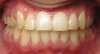

• Orthodontic expansion of the maxillary and mandibular dental arches (Figure 6 and Figure 7).

(6.) Orthodontic dental arch and airway expansion. Images courtesy of Mark Farina, DMD.

Figure 6

(7.) Orthodontic dental arch and airway expansion. Images courtesy of Mark Farina, DMD.

Figure 7